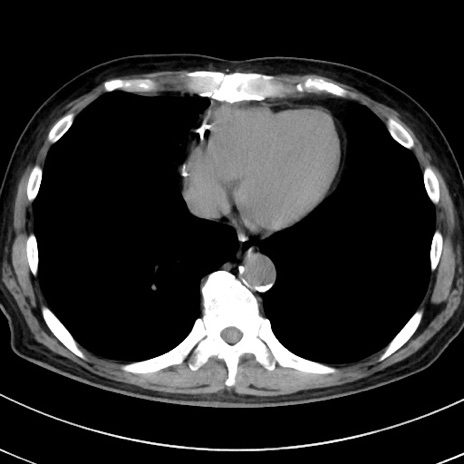

症例38(横断像)

【症例】70歳代 男性

【主訴】腹痛・嘔吐

【現病歴】昨晩より、嘔吐・腹痛あり。今朝になっても嘔吐あり。来院。

【既往歴】心臓バイパス手術、開腹胆摘、腸閉塞

【身体所見】BP 107/71mmHg、HR 116/min、腹部:平坦、軟、下腹部に軽度圧痛あり。反跳痛なし。

【データ】WBC 15100、CRP 0.32